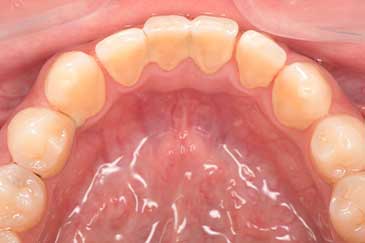

CASE 8

Before

After

基本情報

| 年齢・性別 | 70歳・男性 |

|---|---|

| 主訴 | 虫歯治療、定期検診 |

| 治療内容 | スケーリング |

| 治療期間 | 60分 |

| 治療費 | 1,500円(保険診療) |

| リスク・副作用 | 知覚過敏、出血 |

| 治療方針 | 今回は歯肉縁上歯石を除去しました。今後はSRPを行い、定期的にクリーニングをしていきます。 |

| 担当者所見 | 歯石を除去して歯根面が露出したことにより、知覚過敏が起こりやすいことをお話ししました。再びプラークや歯石がつかないようにセルフケアの重要性をお伝えしました。 |